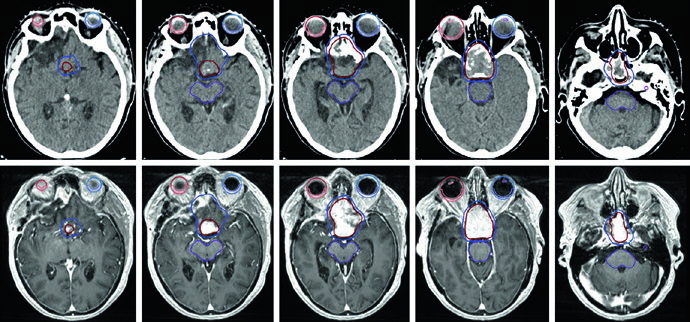

O caso da Figura 29.15 demonstra um cenário mais complexo: tumor glômico recorrente no bulbo jugular esquerdo após embolização e ressecção, tratado com 54 Gy em 30 frações. O GTV foi gerado co-registrando imagens de RM do diagnóstico inicial e da recorrência, incluindo a extensão original da doença, alterações pós-operatórias, leito tumoral e doença recorrente com cobertura até a base do crânio. Margem de 0,3 cm definiu o PTV. Múltiplos OARs — tronco encefálico, mandíbula, parótidas, medula com PRV, parede orofaríngea, cavidade oral e lábios — foram cuidadosamente delineados.